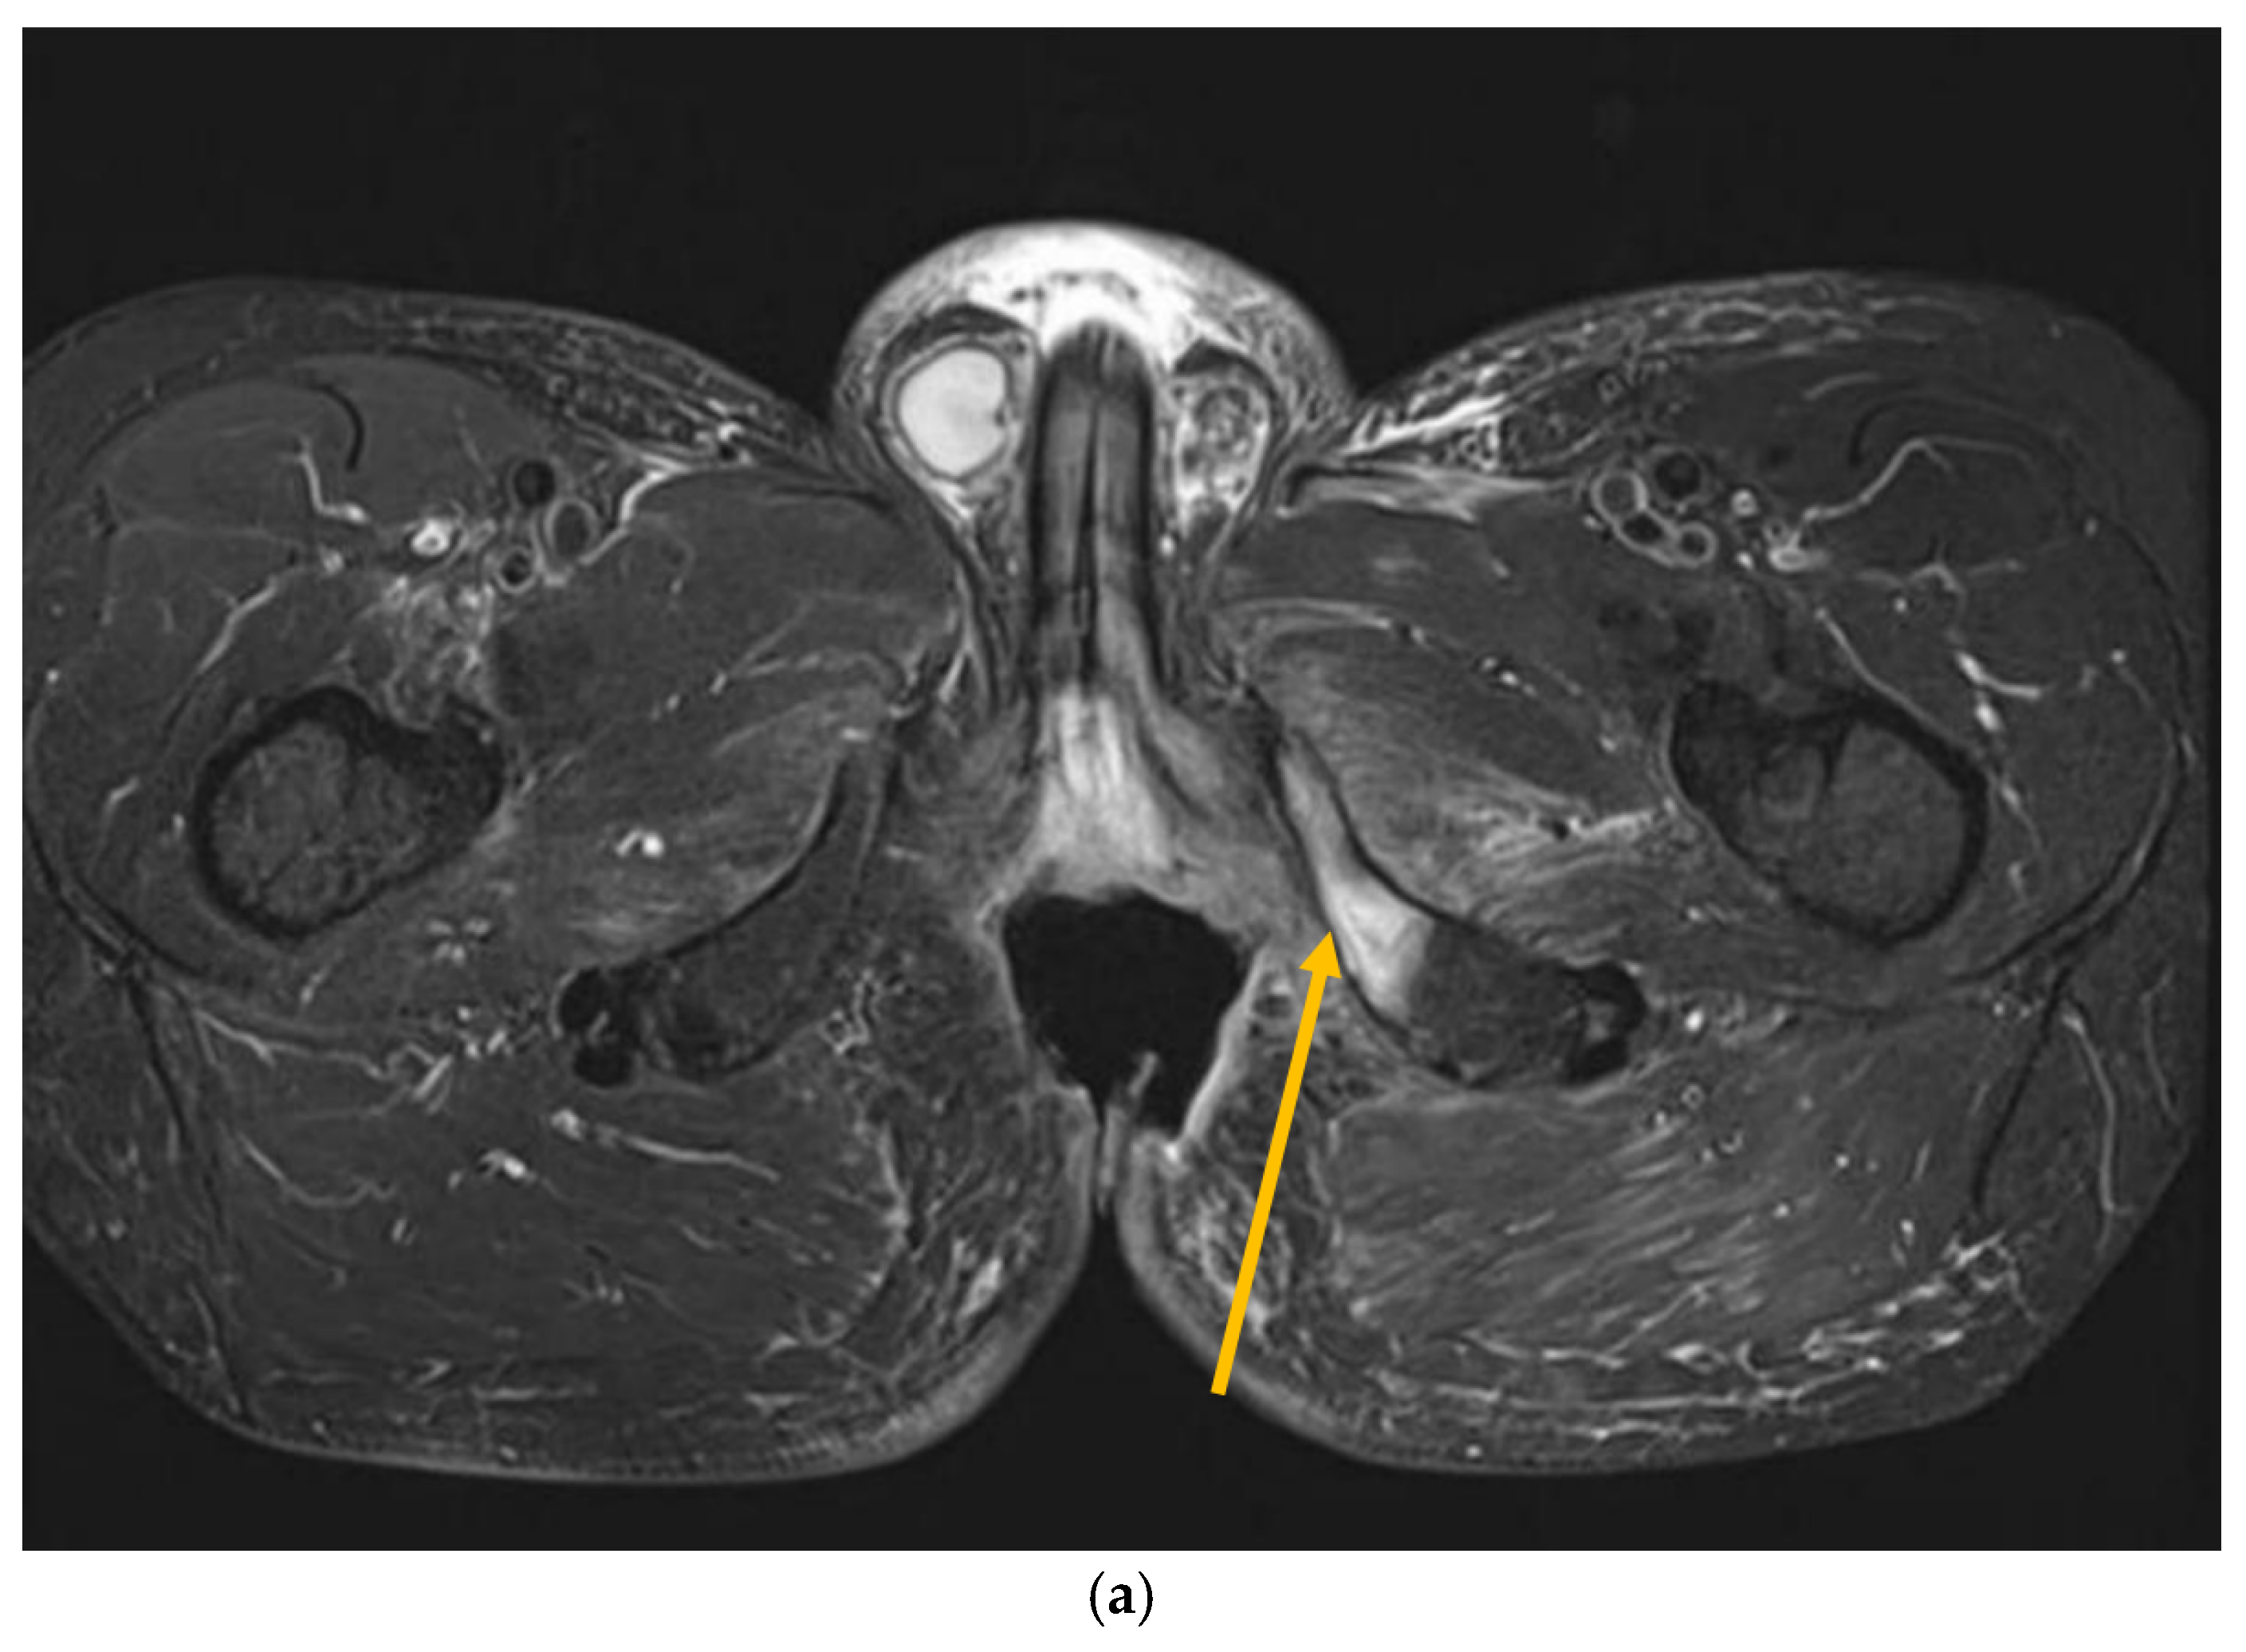

Recently, inflammatory reactions adjacent to the necrosis have slowly progressed to the lower arm of the left pubic and ischium bone and have induced mild osteomyelitis demanding antibiotic and analgesic treatment (Figure 2 and Figure 3). The osteonecrotic focus within the right femoral head and acetabulum is now stable, asymptomatic, and painless.

Figure 3.

MRI scans 26 years after radiotherapy: T1-weighted axial MRI scan shows vast perineal and anal defects progressing to the left lower arm of the pubis with signs of induced osteomyelitis (orange arrow) (a); T2-weighted sagittal scan shows vast perineal and anal defects including absence of anal sphincter (yellow arrow) (b); and T1-tse weighted axial scans show the osteoradionecrosis of the right hip (blue arrow) (c).